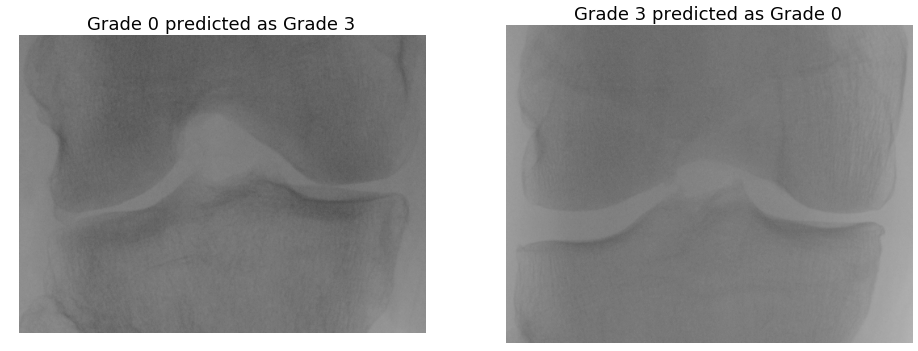

Figure 10 shows some examples of mis-classifications: grade 1 knee joints predicted as grade 0, 2, and 3. Figure 11 shows the mis-classifications of knee joints categorized as grade 0, 2 and 3 predicted as grade 1. These images show minimal variations in terms of joint space width and osteophytes formation, making them challenging to distinguish. Even for the more serious mis-classifications in Figure 12, e.g. grade 0 predicted as grade 3 and vice versa, do not show very distinguishable variations.

Figure 12: An instance of more severe mis-classification: grade 0 and grade 3